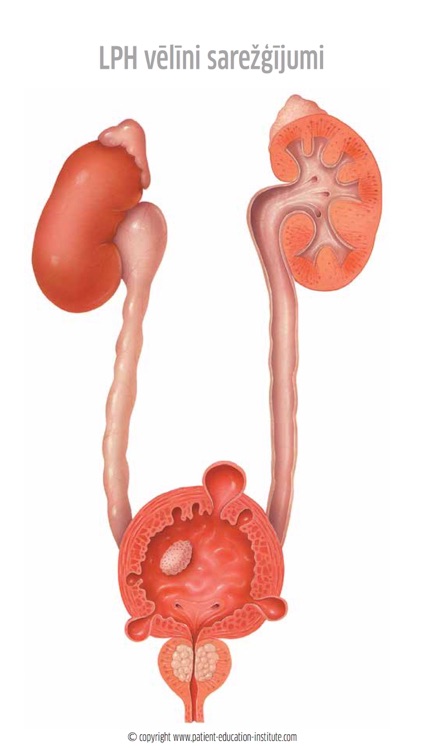

Containing 100s of medical illustrations, the patient-education-institute app is a unique visual aid that helps health care professionals enhance the quality of conversations with their patients. Each clinical situation is presented in a well-structured manner with simple illustrations, icons and short supporting texts.

Containing 100s of medical illustrations, the patient-education-institute app is a unique visual aid that helps health care professionals enhance the quality of conversations with their patients. Each clinical situation is presented in a well-structured manner with simple illustrations, icons and short supporting texts.

Simplicity and Structure

To every patient a consult is a very stressful situation in which his/her capability to absorb information is very limited. That's why our materials excel in presenting each clinical situation as simply as possible, with plenty of high-quality yet simple-to-understand illustrations that adequately support your explanation but leave out any unnecessary complications.